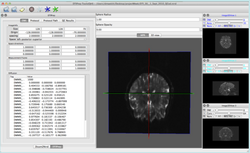

Slicer4 Diffusion Tensor Imaging Tutorial

- The Diffusion Tensor Imaging Tutorial course guides through the basics of loading Diffusion Weighted images in Slicer, estimating tensors and generating fiber tracts.

- Author: Sonia Pujol, Ph.D.

- Audience: End-users and developers

- Modules: Data, Volumes, DWI to DTI Estimation, Diffusion Tensor Scalar Measurements, Editor, Markups,Tractography Label Map Seeding, Tractography Interactive Seeding

- Based on: 3D Slicer version 4.5

- The DTI dataset contains an MR Diffusion Weighted Imaging scan of the brain.